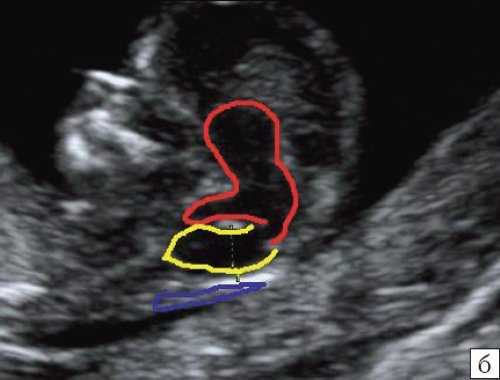

б) Вид "осьминожки":

- красный цвет - диэнцефалон (таламус), со стволом мозга (верхняя ножка) и IV желудочком (нижняя ножка);

- желтый цвет - большая цистерна головного мозга;

- синий цвет - воротниковое пространство.

Новый ультразвуковой маркер в изучении нормальной ультразвуковой анатомии головного мозга плода в срок 11-14 недель беременности

Особенности визуализации изложенных выше структур в данном сроке позволили нам выделить и назвать новый ультразвуковой маркер нормальной ультразвуковой анатомии мозга плода. Структуры головного мозга плода в этой области схожи с осьминогом, у которого есть голова и две приблизительно равновеликие по диаметру ножки, представляющие собой ствол мозга и IV желудочек. Ниже ножек "осьминожки" визуализируется 2 "подушки осьминожки" - это два анэхогенных пространства - большая цистерна и воротниковое пространство (рис. 2, б).

Так как речь идет о сроках первого скрининга, т.е. раннего осмотра, новый ультразвуковой маркер мы назвали "осьминожкой" (рис. 3).

а) Стрелками указана голова "осьминожки" - диэнцефалон (таламус).

б) Красный цвет - диэнцефалон (таламус), со стволом мозга (верхняя ножка) и IV желудочком (нижняя ножка); желтый цвет - большая цистерна головного мозга; синий цвет - воротниковое пространство.